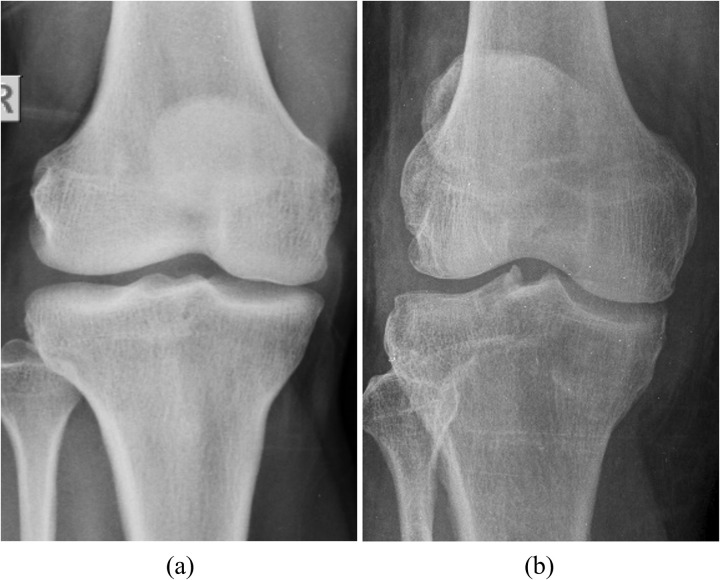

Osteoporosis is a prevalent bone disease characterized by reduced bone density and an elevated risk of fractures, especially in older adults and postmenopausal women. The clinical consequences of osteoporotic fractures extend beyond pain and disability, contributing substantially to morbidity, mortality, and healthcare costs. Early intervention and accurate detection is therefore essential to improve patient outcomes. This paper introduces an advanced deep-learning methodology to enhance the accuracy and efficiency of osteoporosis detection through knee X-ray analysis. The proposed approach integrates features from two pre-trained models, DenseNet169 and Vision Transformer (ViT), with a custom-designed Attention Model (AM) to capture detailed spatial and channel-specific information from the input images. These fused features are then fed into a fully connected neural network to classify the images as osteoporotic or normal. The results indicate significant improvements in classification accuracy, achieving a high accuracy rate on previously unseen test data. The proposed model achieves superior performance over existing methods and other recent models for osteoporosis detection, with an accuracy of 0.8611, specificity of 0.9474, and precision of 0.9286. Our approach effectively combines convolutional and transformer-based representations, enabling extraction of both local and global features for comprehensive bone characterization. These findings highlight the model's potential to support early diagnosis, timely intervention, and improved patient care in osteoporosis management.